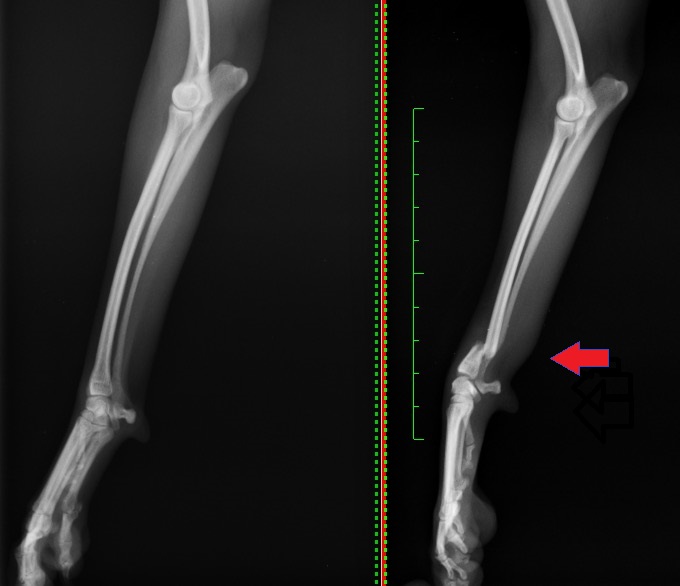

1、2枚目は前腕部(手根~肘)の骨(橈骨・尺骨)のX線写真になります。

1枚目が正面から撮影したX線写真、2枚目が横から撮影したX線写真です。赤矢印が骨折部位になります。

この子は左前肢の橈骨尺骨骨折でしたが、骨折していない右前肢を同条件下で撮影し比較することにより、

より異常所見が検出しやすくなります。